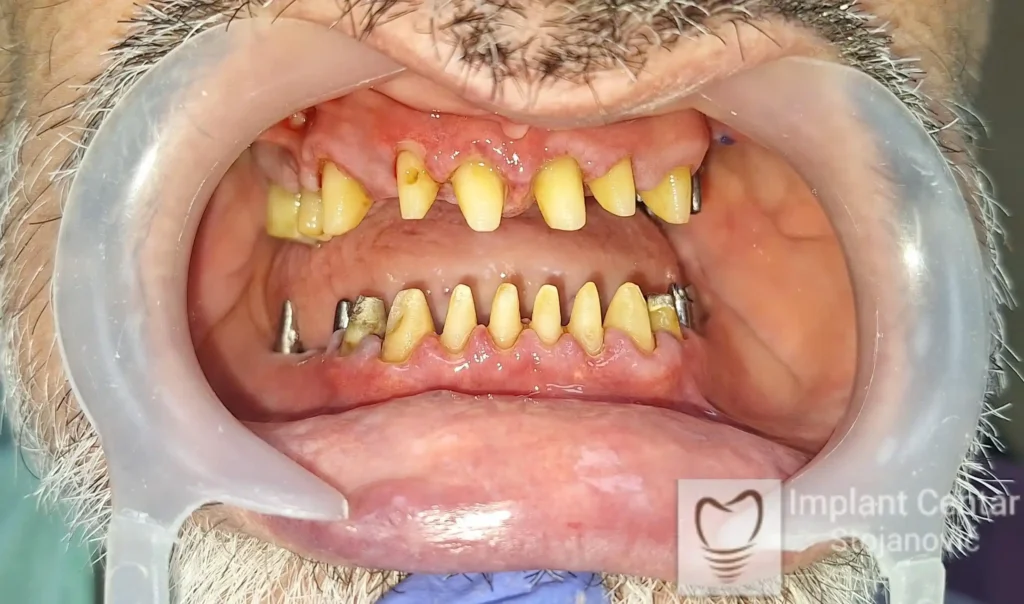

Pacijent sa rascepom usne, nepca i alveolarnog grebena uspešno je rehabilitovan fiksnim protetskim radom na implantatima. Pre dolaska u našu ordinaciju, pacijent je u gornjoj vilici nosio totalnu protezu preko preostalih zuba, dok je u donjoj vilici bio zbrinut parcijalnom mobilnom protezom. Tokom višegodišnje potrage za adekvatnim rešenjem, pacijent nije uspeo da pronađe zadovoljavajuću terapijsku opciju ni u zemlji ni u inostranstvu.

Pacijent je došao u našu ordinaciju sa totalnom protezom u gornjoj vilici i uznapredovalom parodontopatijom preostalih zuba u donjoj vilici.

Pacijent kod koga je, zbog uznapredovale parodontopatije, bilo indikovano vađenje svih preostalih zuba.

Na slikama 1 i 2 prikazan je klinički izgled pacijenta pre početka terapije. Nakon detaljnog kliničkog pregleda, analize radioloških snimaka, kao i razgovora sa pacijentom o njegovim željama i očekivanjima, izrađen je sveobuhvatan plan terapije. Terapija je podrazumevala vađenje preostalih zuba, ugradnju dentalnih implantata i izradu fiksnog protetskog rada na implantatima.